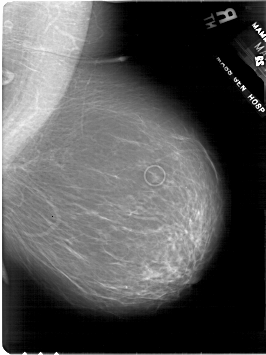

A_1801_1.LEFT_MLO

LEFT_MLO LINES 6601 PIXELS_PER_LINE 4981 BITS_PER_PIXEL 12 RESOLUTION 43.5 OVERLAY

FILE: A_1801_1.LEFT_MLO.OVERLAY

TOTAL_ABNORMALITIES 1

ABNORMALITY 1

LESION_TYPE MASS SHAPE LOBULATED MARGINS CIRCUMSCRIBED

ASSESSMENT 4

SUBTLETY 5

PATHOLOGY BENIGN

TOTAL_OUTLINES 1

BOUNDARY